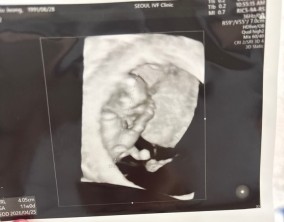

기대하지 않았던 두 줄, 그리고 끝까지 이어진 믿음

이경훈 원장님이 아니었다면 소중한 아기를 품을 수 없었을 것이라 생각합니다. 자궁 후굴이 심한 제 상황을 고려해 여러 방법을 연구하고 시도해 주신 덕분에 지금의 결과를 만날…